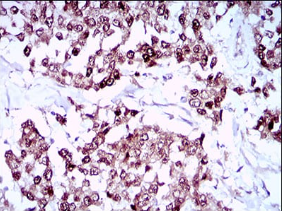

IHC    1/200 - 1/1000